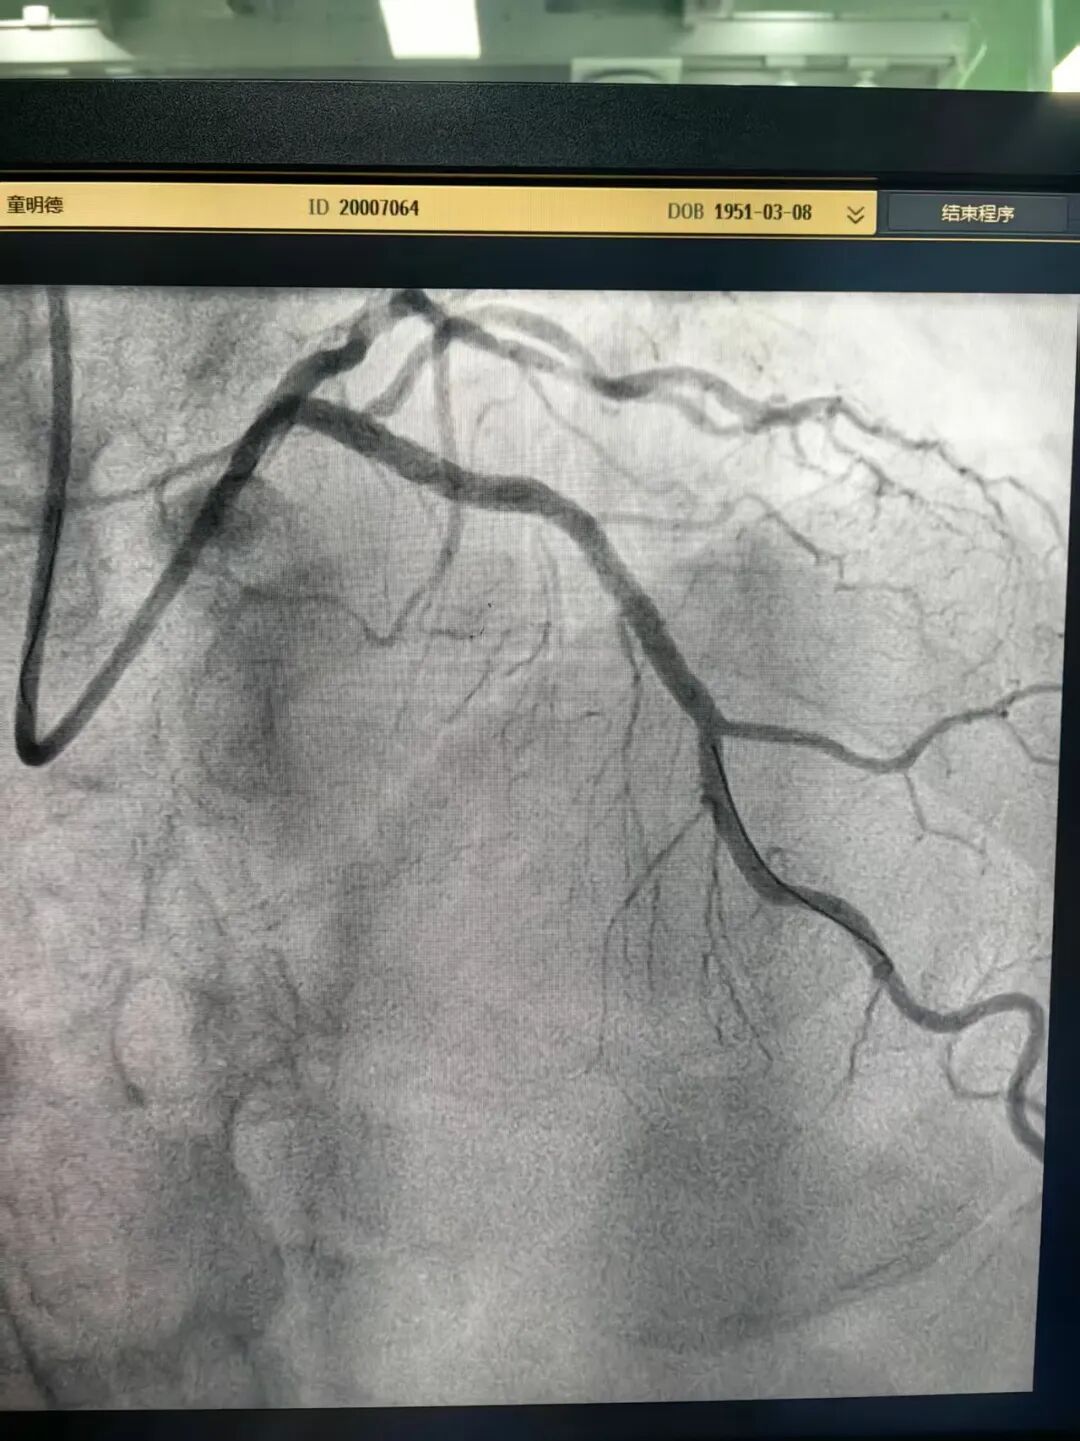

此外,一名74岁的男性患者因PCI(经皮冠脉介入术)术后17年再发胸痛前来就诊。冠脉造影显示他前降支近端模糊病变,肉眼判定其狭窄程度并不严重,但患者症状典型。

林茂欢副主任医师带领团队使用IVUS(血管内超声)技术辅助诊断,证实该处管腔面积明显狭窄,最终为他精准植入两枚支架。术后,患者管腔面积显著增加,症状完全缓解。这一手术的成功实施,标志着花都院区冠脉精准介入诊治迈入了新的阶段。

术前照片